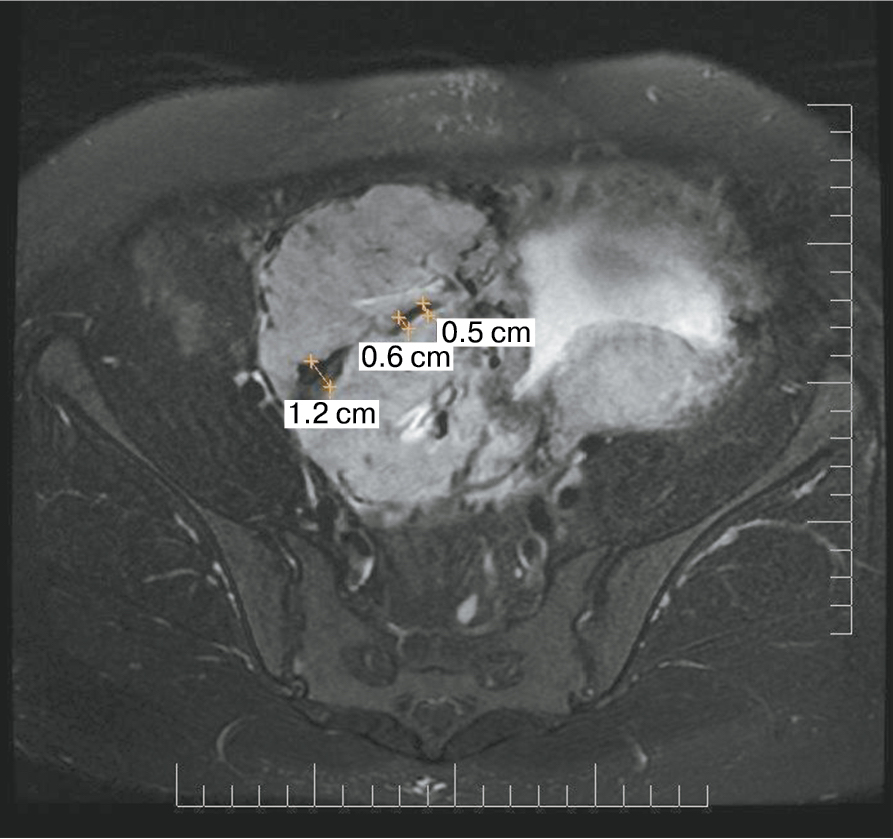

Также стоит выделить особый тип плацентарной гиперваскуляризации, а именно включение в плацентарной ткани изменений по типу «обнаженного сосуда» (рис. 1, 2). Мы провели анализ встречаемости данного признака среди наших пациентов. Любопытным наблюдением явилось то, что данный симптом в нашей выборке встречался только при наличии placenta percreta – 6 случаев, а именно при поражении параметриев, и не встречался при плацентарной инвазии, ограниченной миометрием. «Мостовидные сосуды» были менее специфичны, тем не менее, их наличие также сопровождало тяжелые формы врастания, обусловленные более глубокой инвазией ворсин хориона, – 8 случаев.

Рис. 1. МРТ placenta percreta, симптом «обнаженного сосуда»

Рис. 2. МРТ placenta percreta, симптом «обнаженного сосуда»

Является ли симптом «обнаженного сосуда» патогномоничным для параметральной инвазии или нет, еще предстоит выяснить; однако в ходе исследования установлена его связь с частотой гистерэктомий в группах с наличием симптома «обнаженного сосуда», что, вероятно, обусловлено мощной сосудистой сетью коллатералей и неоангиогенезом. Во всех случаях обнаружения данного признака впоследствии была выполнена вынужденная гистерэктомия (рис. 3–6, пациентка Н., 37 лет).